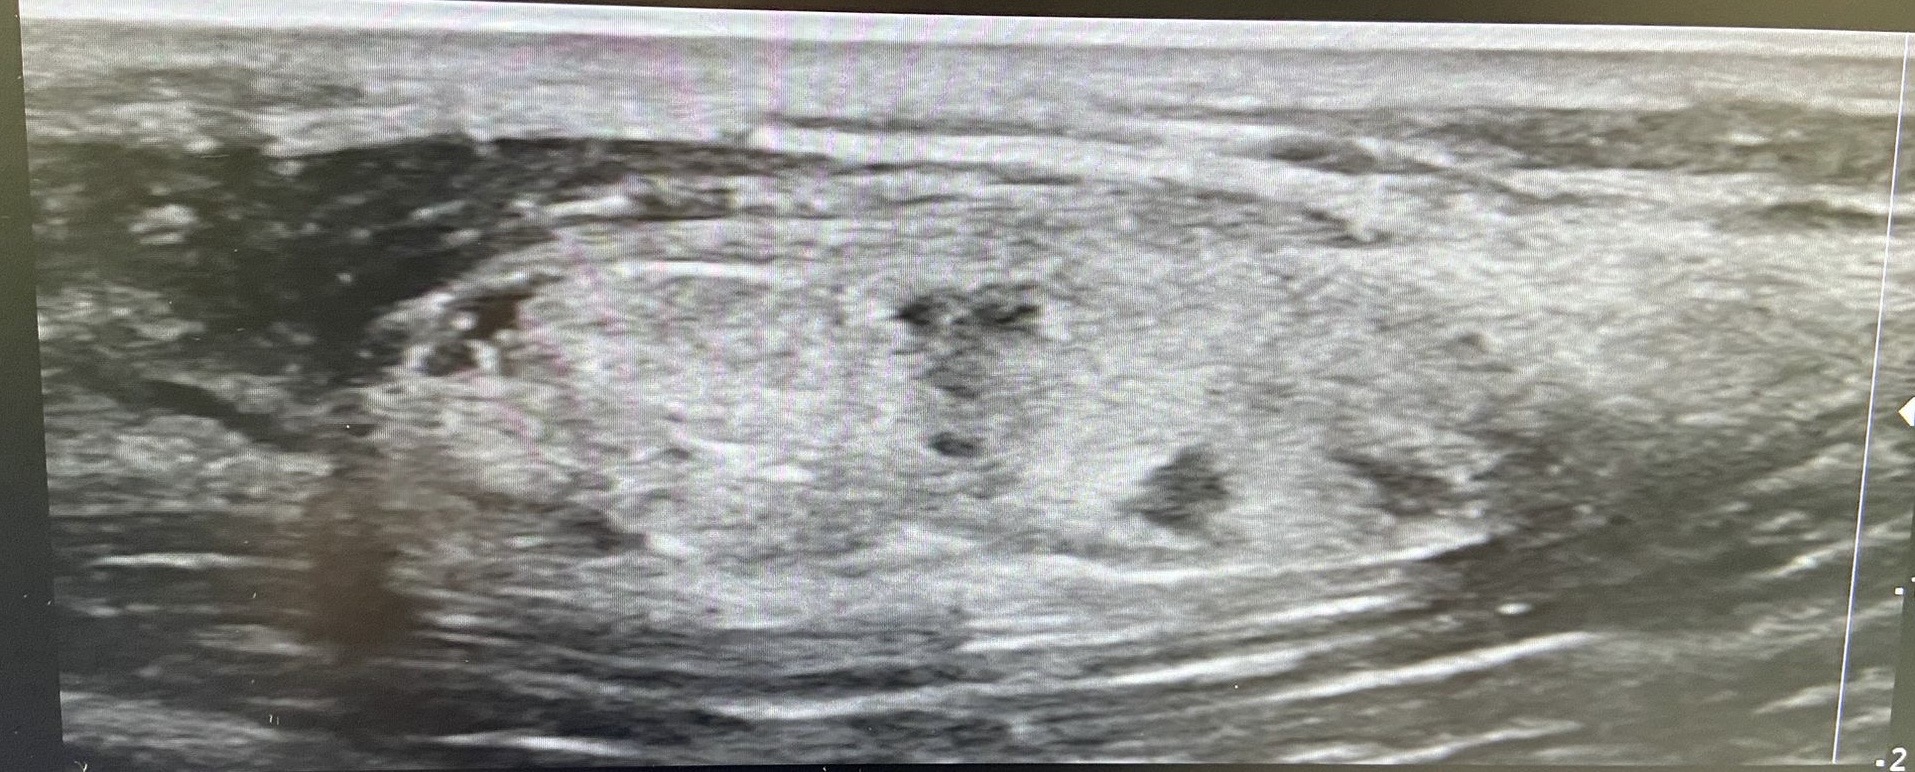

Ecografía clínica en consulta: Se observa una lesión bilobulada, isoecoica respecto a la grasa, levemente heterogénea, de bordes bien definidos, de aproximadamente 33 × 11 × 18 mm. En el estudio Doppler color se identifican estructuras vasculares en su interior.

Ecografía reglada de partes blandas: Informe compatible con lipoma atípico vs liposarcoma bien diferenciado en gemelo externo de pierna derecha. Se recomienda realizar RMN con contraste.